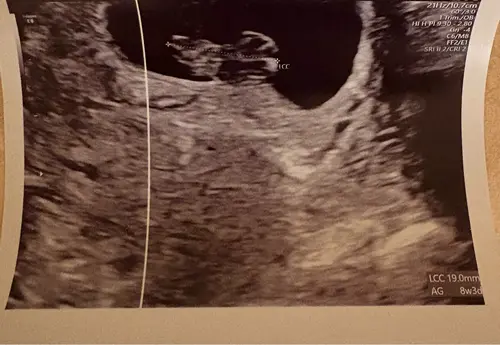

Dan doe ik ook maar mee, wat denken jullie bij die van mij. Is inwendige echo

Dan doe ik ook maar mee, wat denken jullie bij die van mij. Is inwendige ec ...

ik denk een meisje 馃┓

Uitwendig! Sorry vergeten te benoemen

ik denk meisje馃┓